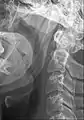

Muscles of the neck. Anterior view.

The stylohyoid ligament is a ligament that extends between the hyoid bone, and the temporal styloid process (of the temporal bone of the skull).

It attaches at the lesser horn of hyoid bone[1][2] inferiorly, and (the apex of[1]) the styloid process of the temporal bone[1][2] superiorly.

The ligament gives attachment to the superior-most fibres of the middle pharyngeal constrictor muscle.[1]

The ligament is adjacent to the lateral wall of the oropharynx.[1]

Inferiorly, it is adjacent to th hyoglossus.[1]